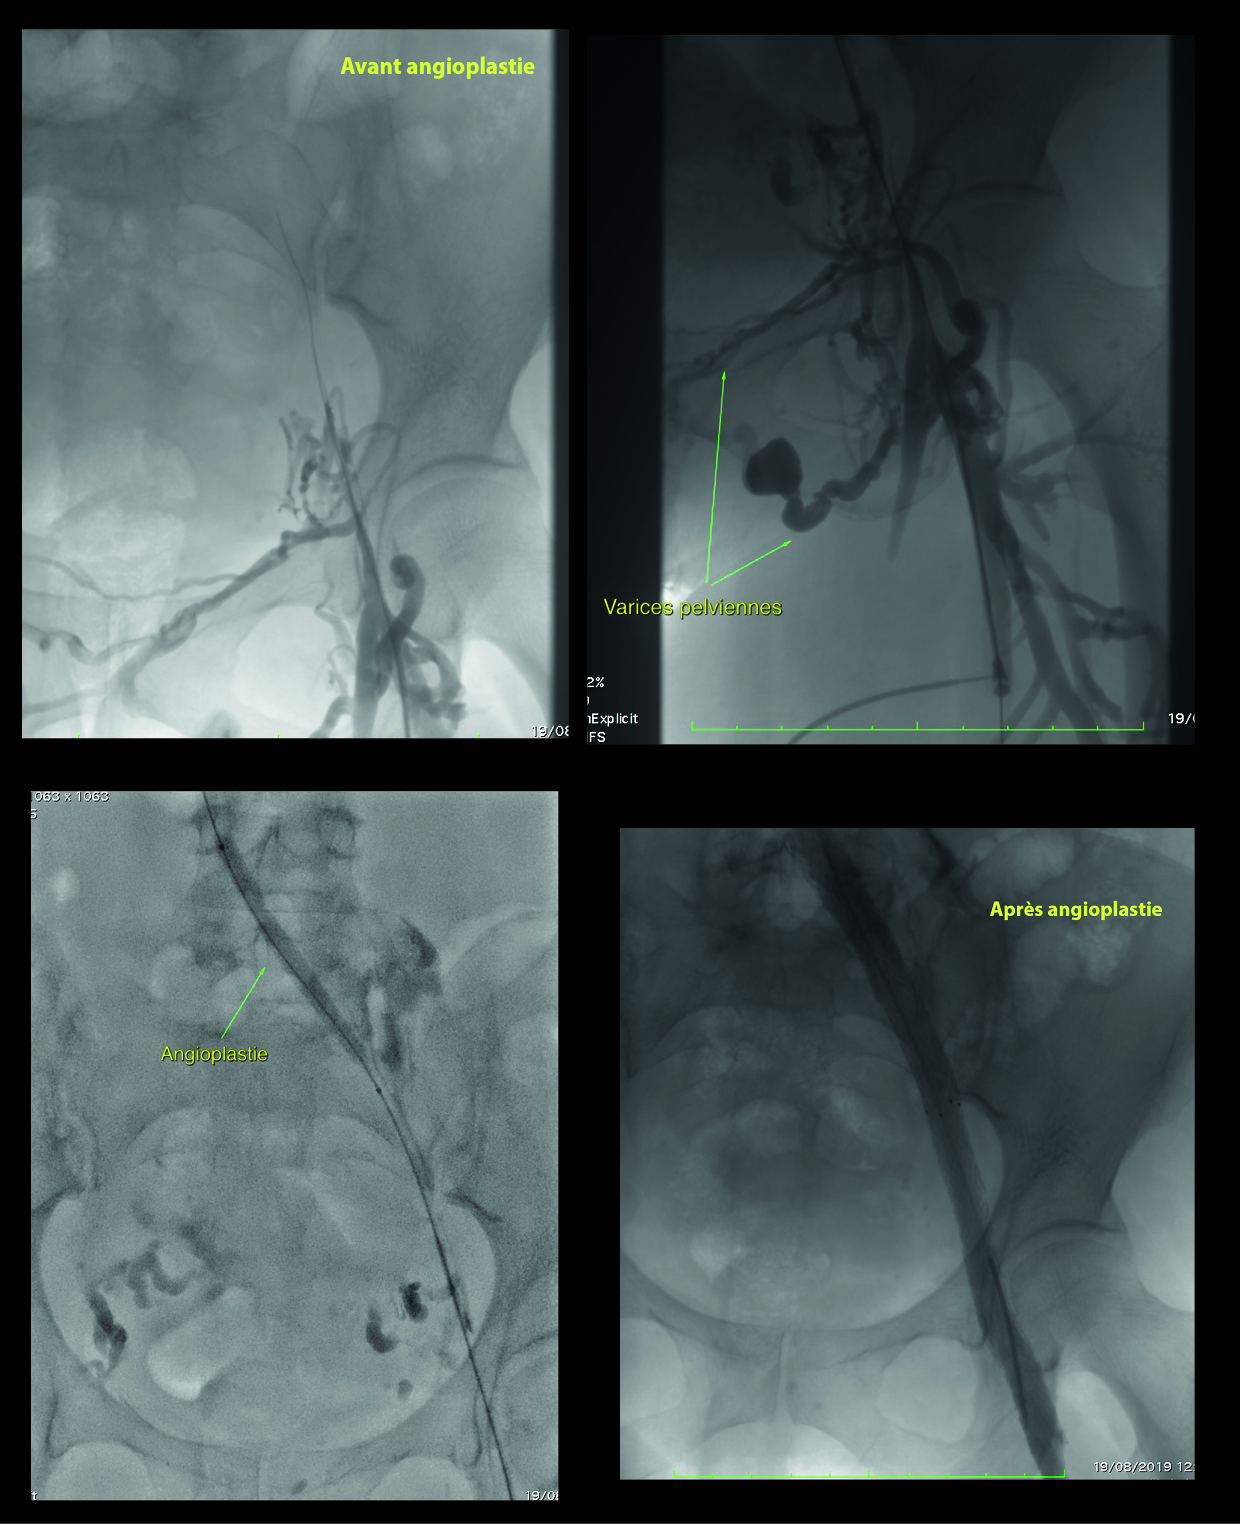

DétailsJeudi 20 juin 2019 "Atelier Angioplastie Périphérique"L’angioplastie périphérique est une spécialité qui évolue avec des pratiques très diverses d’un opérateur à l’autre…